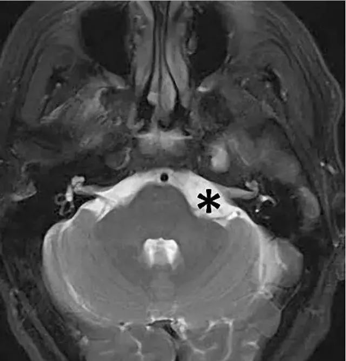

術(shù)前MRI:從腦幕下表面向左小腦橋腦角產(chǎn)生大的均勻增強(qiáng)病變,引起顯著的腦干壓迫,出現(xiàn)面部麻木和步態(tài)失衡

診斷:橋小腦角區(qū)腦膜瘤

手術(shù)方案:左側(cè)乙狀竇后開(kāi)顱手術(shù)切除腫瘤

術(shù)后情況:手術(shù)順利,腦膜瘤得以全切,沒(méi)有新的術(shù)后神經(jīng)功能缺損,腦干壓迫消失。術(shù)后第4天出院回家,術(shù)后1個(gè)月,步態(tài)失衡和左側(cè)面部麻木消失。其后到現(xiàn)在的4年間,隨訪未見(jiàn)腦膜瘤復(fù)發(fā),老人一切生活正常。

圖 1 *號(hào)所標(biāo)位置附近即為橋小腦角區(qū),此處可見(jiàn)

橋小腦角區(qū)多為軸外腫瘤,以聽(tīng)神經(jīng)瘤常見(jiàn),以及腦膜瘤,三叉神經(jīng)瘤,另外可見(jiàn)膽脂瘤,蛛網(wǎng)膜囊腫,血管母細(xì)胞瘤,動(dòng)脈瘤,海綿狀血管瘤,轉(zhuǎn)移瘤,以及發(fā)生于小腦及腦干的腦內(nèi)腫瘤突入橋小腦角區(qū)。

橋小腦角(CPA)區(qū)腦膜瘤一般起源于覆蓋在巖錐后表面的硬膜,位于三叉神經(jīng)的外側(cè)。Cushing和Eisenhardt在1938年最早將這類(lèi)腫瘤描述為“偽聽(tīng)神經(jīng)瘤”。大部分橋小腦角區(qū)腦膜瘤起源于第Ⅴ、Ⅶ/Ⅷ、Ⅸ和Ⅹ顱神經(jīng)的后方,這些神經(jīng)被腫瘤推擠向前方且與腫瘤之間存在完整的蛛網(wǎng)膜分隔,且腫瘤近中線側(cè)還有豐富的血管結(jié)構(gòu)。也正因其位置的復(fù)雜性,決定著手術(shù)切除的極大難度。